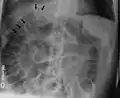

Pneumoperitoneum seen on X-ray with the patient lying on his left side.

Double wall sign. This is a secondary sign of pneumoperitoneum. Patient is supine, and air within the abdomen and lumen of the bowel accentuate both sides of the bowel wall.